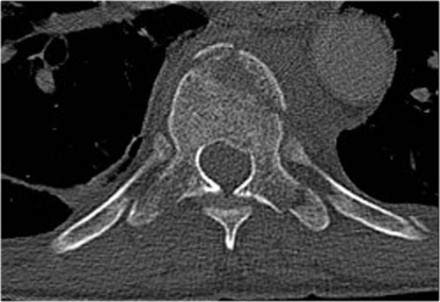

The images are of a patient with a typical bamboo spine as a result of ankylosing spondylitis.

After a fall on his back no fracture was seen on the x-rays.

However the CT shows a thin fracture line through the anterior side of the vertebral body and also through the spinous process.

Continue with the MR-images.